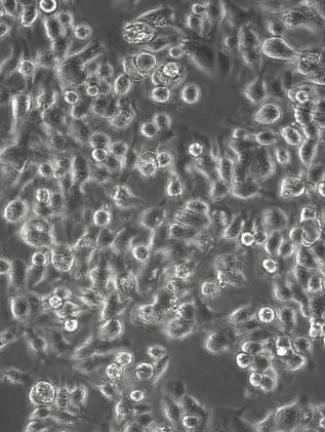

明美活细胞成像仪可长时间无干扰观测肿瘤细胞增殖、迁移等行为,结合无线操控功能,为抗癌药物筛选与机制研究提供高效平台。

明美实拍乳腺癌细胞